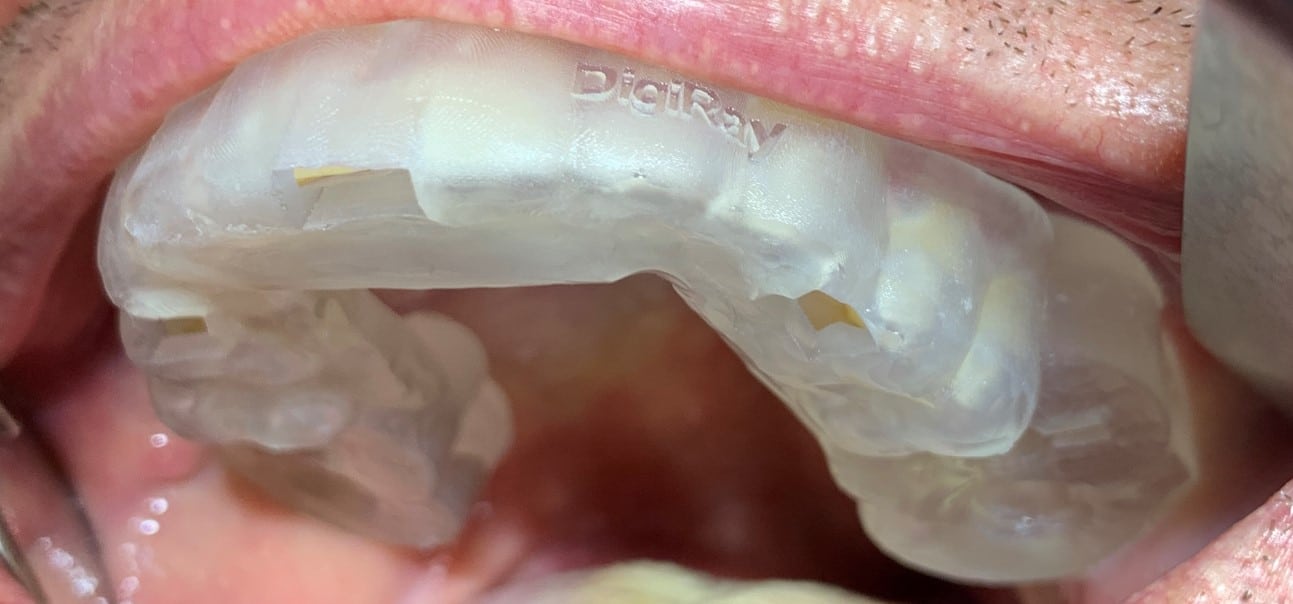

Împreună cu pacientul, am optat pentru inserarea implantelor cu ajutorul ghidului chirurgical pentru a plasa implantul în poziția protetică ideală și pentru a permite realizarea coroanelor insurubate pe implant. A fost efectuată scanarea digitală a arcadelor și a ocluziei pacientului, iar împreună cu tehnicianul radiolog de la DigiRay a fost suprapus fișierul .stl al amprentei digitale peste fișierul .dcm de la CBCT, utilizând software-ul 3Shape.

S-a planificat individual poziția și axul de inserție al fiecărui implant.